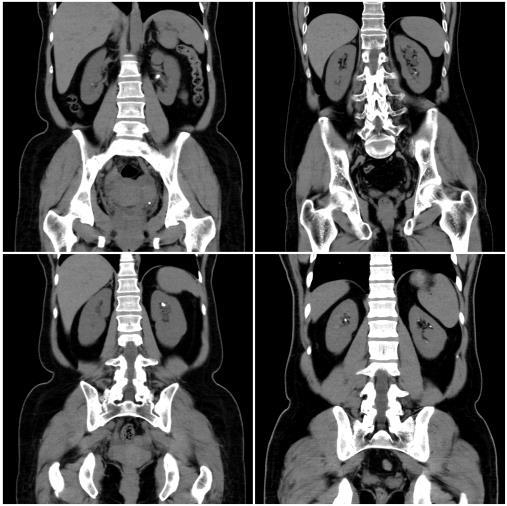

The dataset comprises CT scan images of kidneys, categorized based on the presence or absence of kidney stones. To ensure consistency in model training, preprocessing techniques such as image resizing, normalization,andaugmentationwereapplied.Theimages were resized to a standard dimension suitable for deep learningmodels,andnormalizationensuredthatpixelvalues remained within an optimal range. Data augmentation techniques were selectively used to enhance model generalizationandpreventoverfitting.

The dataset used for training contains CT scan images labeled according to the presence of kidney stones. These imageswerepreprocessedandaugmentedtoensurethatthe modelcouldgeneralizewellacrossvariousunseendata.The preprocessing steps involved resizing images to 224x224 pixels, which is the required input size for MobileNetV2. Normalizationwasappliedtoscalepixelvaluestoarange suitable for training deep learning models. Data augmentation techniques, such as random rotations, flips, and contrast adjustments, were used to increase the diversity of the dataset, which helps the model perform betterunderreal-worldconditionswhereimagesmayvary inorientation,brightness,andnoise.